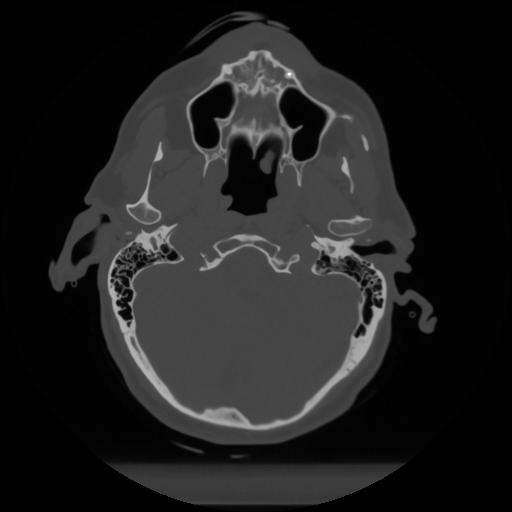

12 P.BLANDAS,,Vol,0.5,P.BLANDAS,,